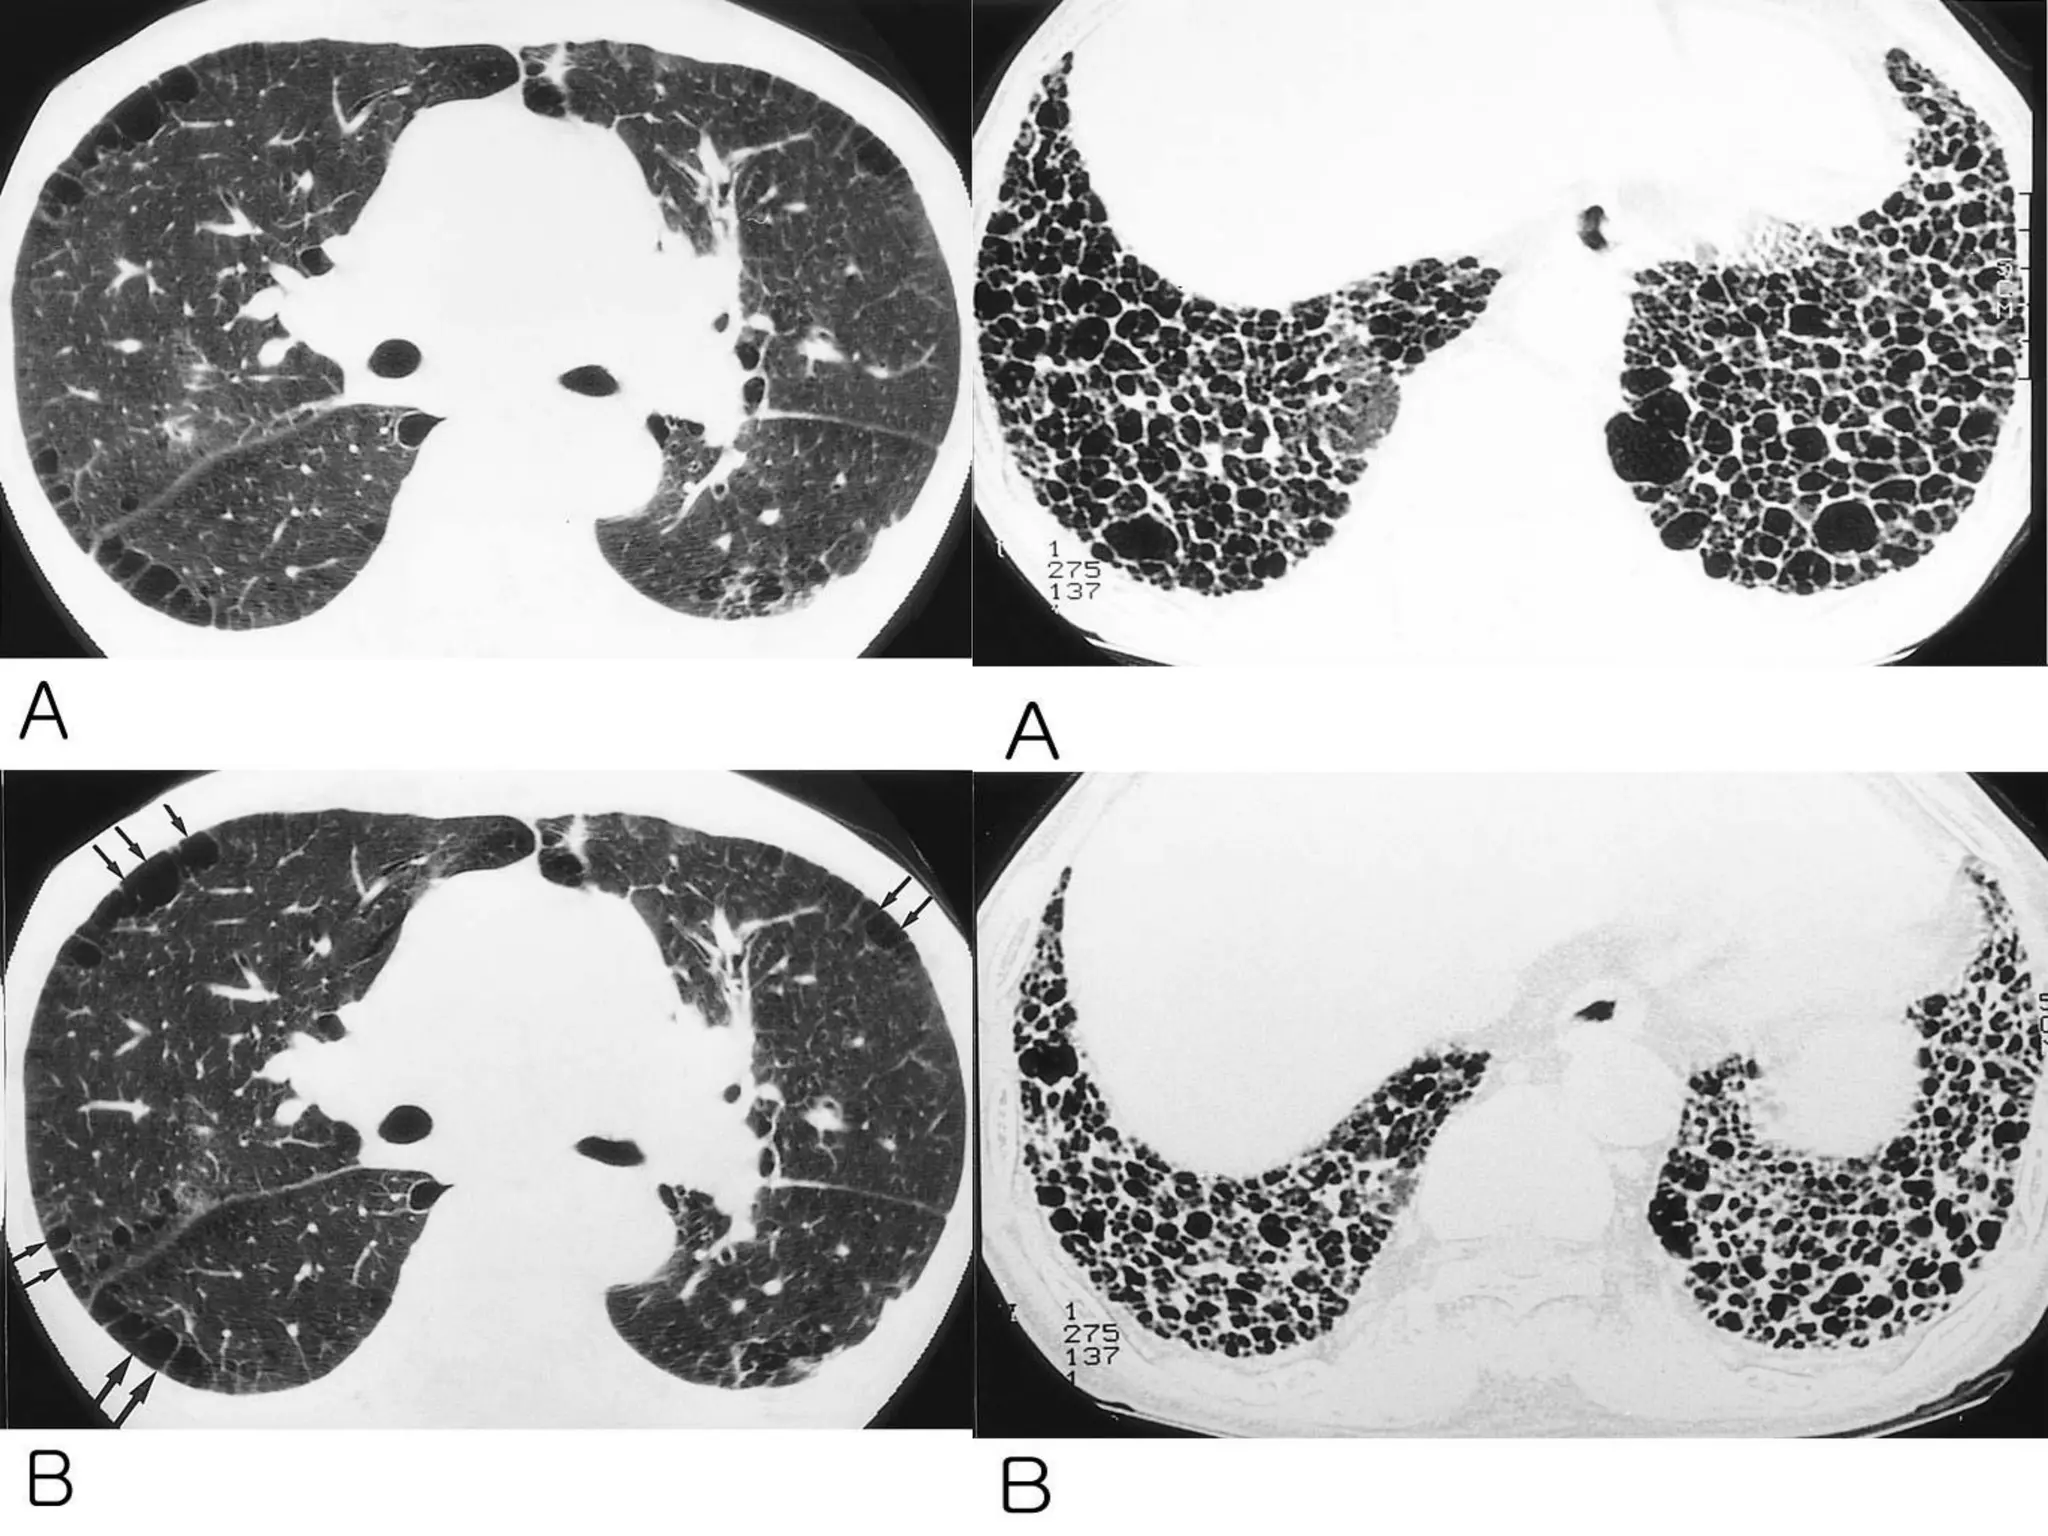

Air Trapping

Air trapping is retention of air in the lung

distal to an obstruction (usually partial). Air

trapping is seen on end-expiration CT

scans as parenchymal areas with less

than normal increase in attenuation and

lack of volume reduction. Comparison

between inspiratory and expiratory CT

scans can be helpful when air trapping is

subtle or diffuse. Differentiation from areas

of decreased attenuation resulting from

hypoperfusion as a consequence of an

occlusive vascular disorder (eg, chronic

thromboembolism) may be problematic ,

but other findings of airways versus

vascular disease are usually present.

Where is the pathology ???????

in the areas with increased density

meaning there is ground glass

in the areas with decreased density

meaning there is air trapping

Pathology in black areas

Airtrapping: Airway Disease

Bronchiolitis obliterans (constrictive bronchiolitis)

idiopathic, connective tissue diseases, drug reaction,

after transplantation, after infection

Hypersensitivity pneumonitis

granulomatous inflammation of bronchiolar wall

Sarcoidosis

Asthma / Bronchiectasis / Airway diseases

Airway Disease

what you see……

In inspiration

sharply demarcated areas of seemingly increased

density (normal) and decreased density

demarcation by interlobular septa

In expiration

‘black’ areas remain in volume and density

‘white’ areas decrease in volume and increase in

density

INCREASE IN CONTRAST

DIFFERENCES

Bronchiolitis

obliterans